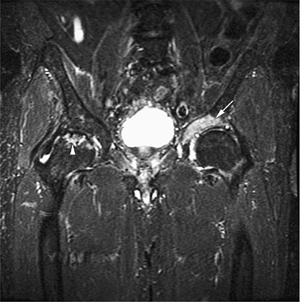

FIGURE 13.25 ● Recurrent tumor after bone marrow transplantation is seen on a coronal STIR image of the pelvis. Hyperintense recurrent tumor (arrow) is involving the acetabulum. Incidentally noted is avascular necrosis of the right femoral head (arrowhead).

|